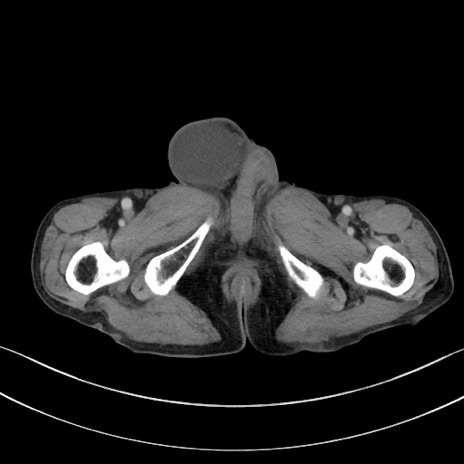

冠状断像

矢状断像

【症例】 70歳代男性

【主訴】右鼠径部腫瘤、疼痛

【現病歴】本日朝より上記主訴あり、受診。

【既往歴】膀胱癌にて膀胱全摘、両側尿管皮膚瘻